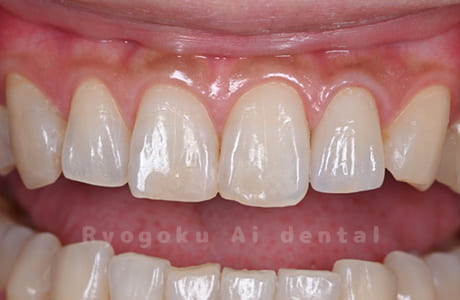

Case01

- 右上1番、不良補綴

- 治療期間

- 3ヶ月

- 治療内容

- 前歯部ジルコニアセラミッククラウン

- 治療費用

- 350,000円

前歯2本の被せ物を希望された患者様です。

<リスク・副作用>

過度の咬合や衝撃で割れることがあります。